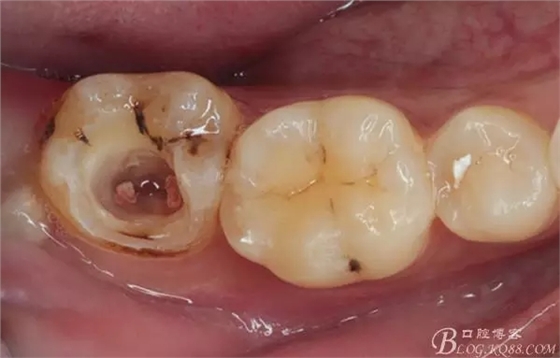

口腔檢查:37頰頜面齲洞,叩(+),探(+),冷熱測試與對照牙對比為敏感。17 27 47 均有不同程度齲壞,無明顯陽性體征。18 28 38 48 呈不同程度傾斜,38 48牙冠部分萌出。全口牙齒排列不整齊,口腔衛(wèi)生較差,牙石(++),部分牙齦發(fā)紅。X線檢查示37牙冠低密度影像累及牙髓,牙周間隙略增寬。

診斷:①37慢性牙髓炎 ②17 27 47頜面齲 ③18 28 38 48阻生牙 ④牙列不齊 ⑤牙齦炎